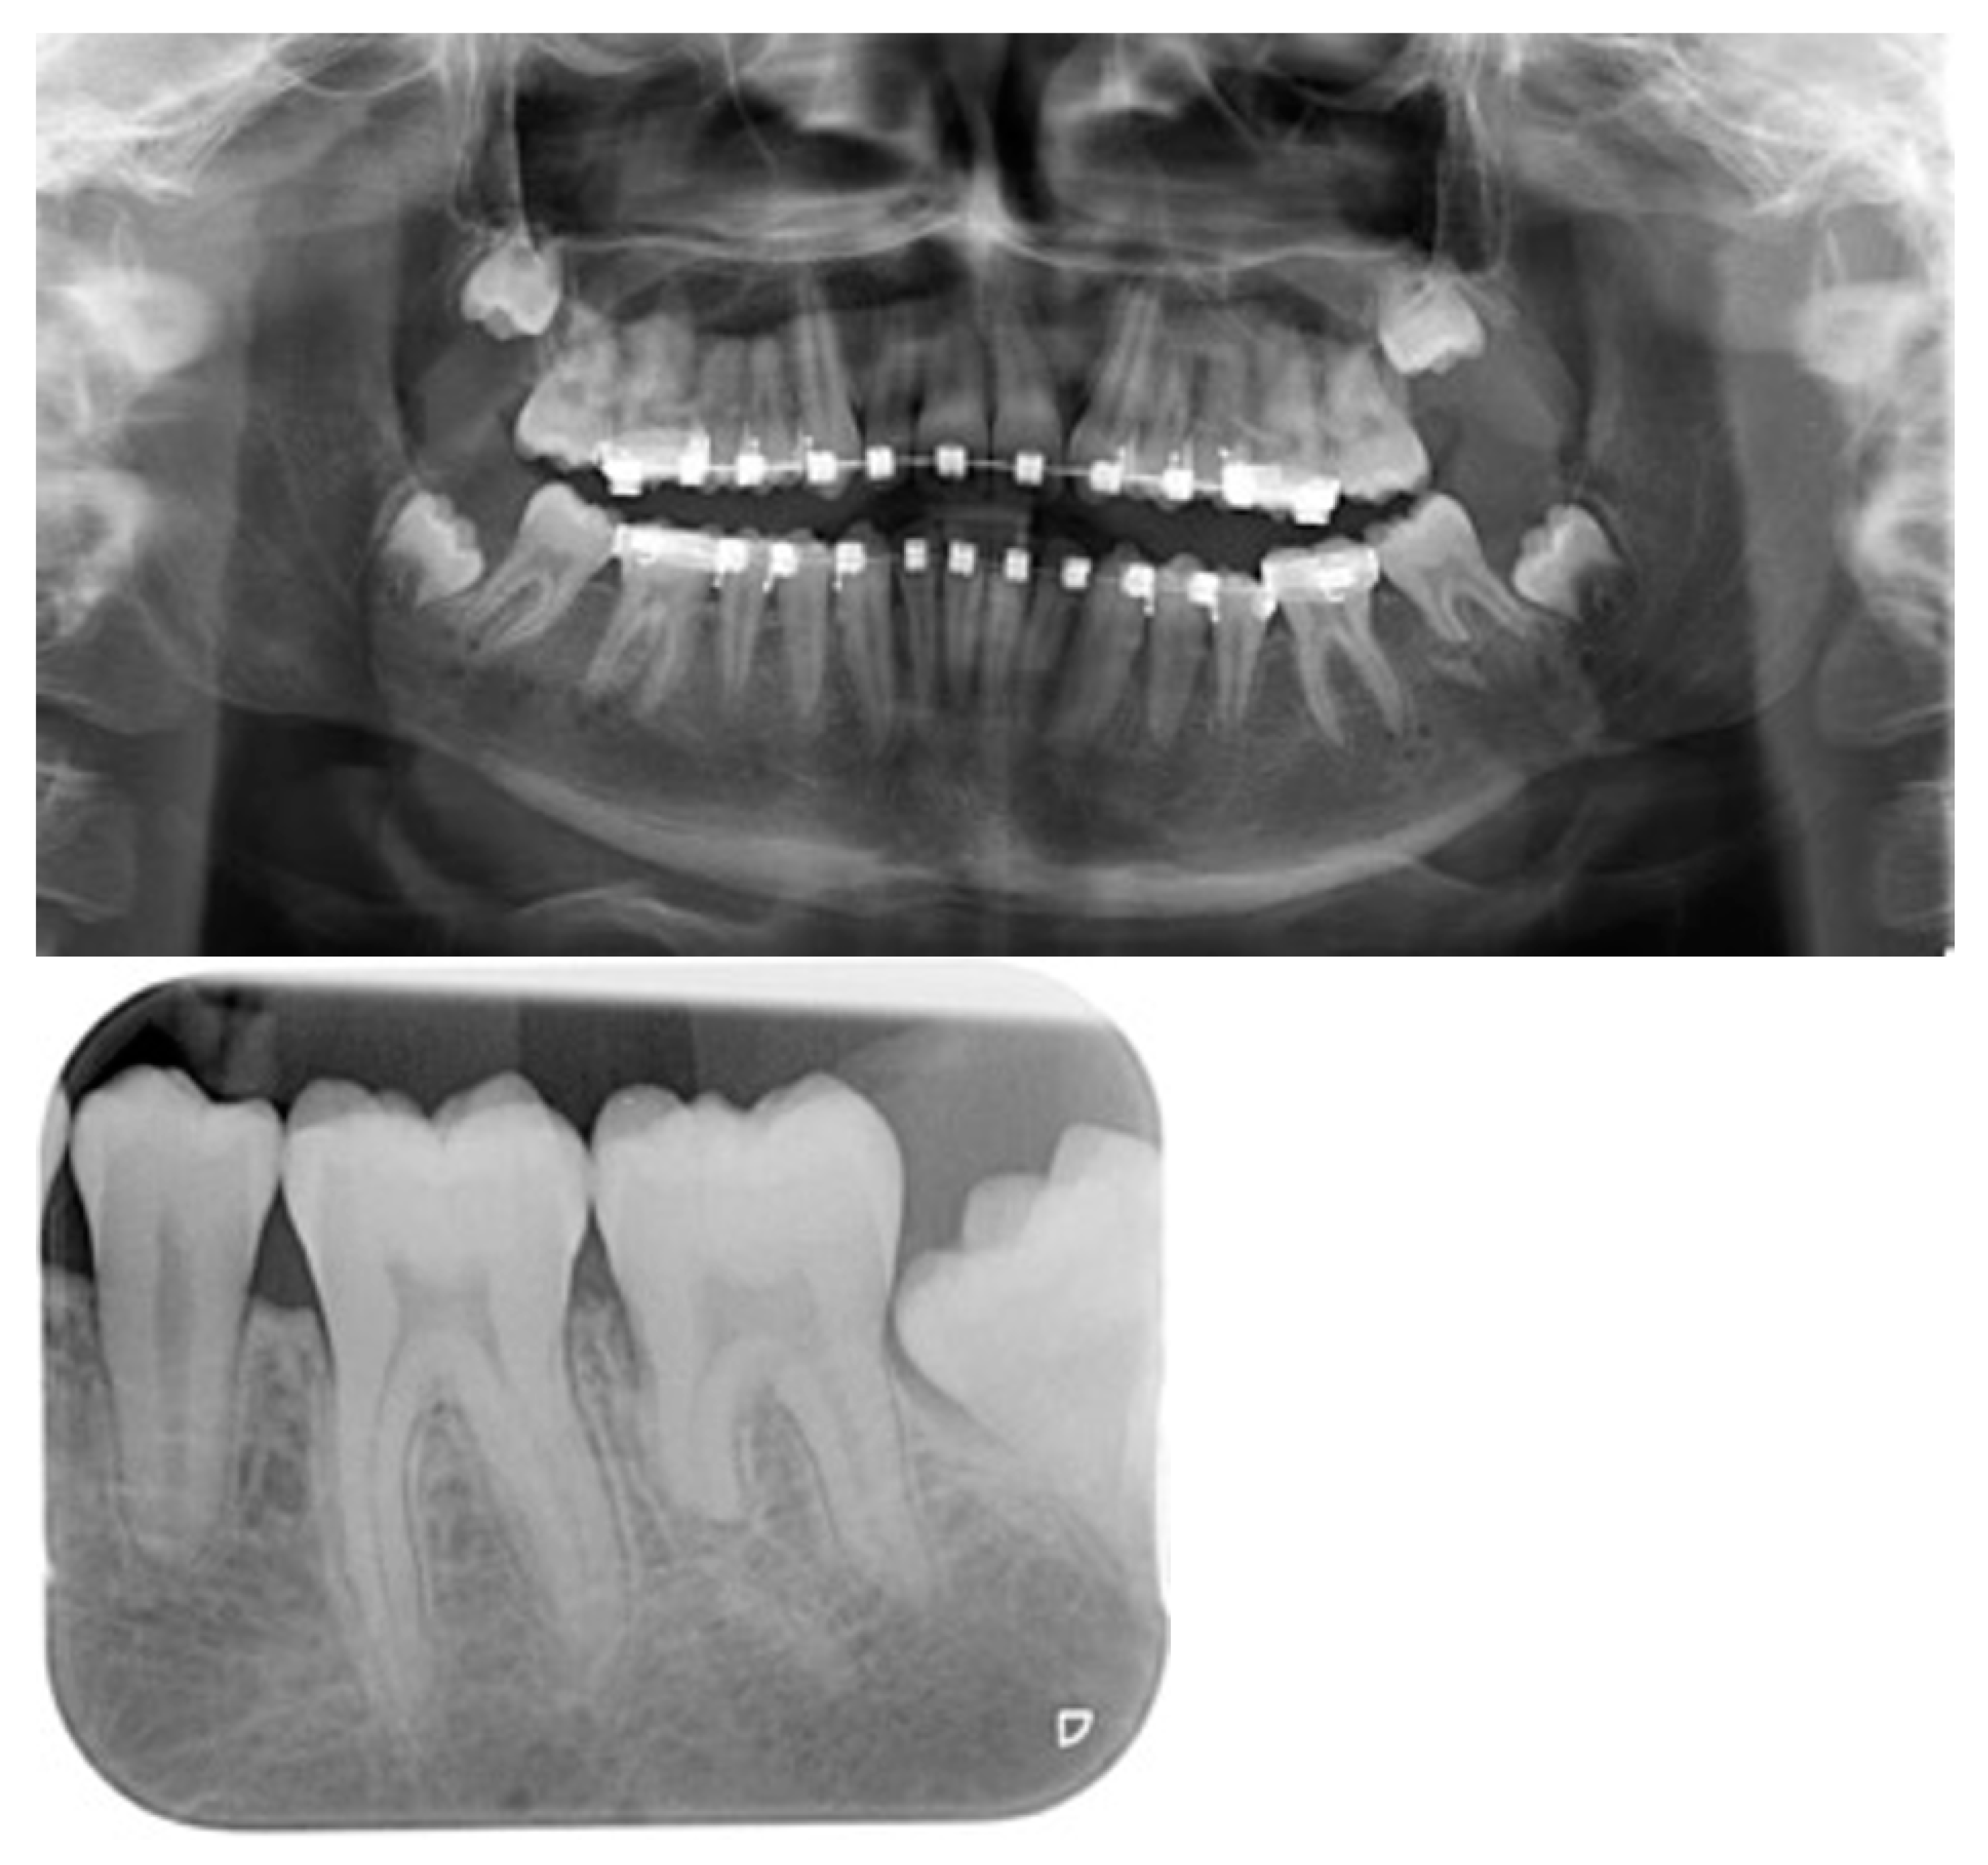

Figure 3.

Radiological follow-up. Panoramic X-rays: (a) Before IMDO. Note the small diastema between the first and second molars of the mandible. (b) Control after distractor placement. Note the symmetrical axis tilt of the distractors. (c) End of active distraction treatment and removal of activation rods for more patient comfort. (d) Bone consolidation 10 weeks after end of distractor activation. (e) After removal of the distractors.

All patients achieved a Class I occlusion, which remained stable until the data collection of this publication. Infections that would have led to premature distractor removal were not observed. However, in one patient an abscess in the region of the activation rod had to be treated by evacuation. No functional impairment of the sensitive function of the third branch of the trigeminal nerve was noted. In nine patients, fractures of the mesial root of the second molar occurred at different levels during osteotomy (Figure 6). Three second molars had to be removed, one molar with root fracture was treated endodontically. Resorptions of the fractured root fragments were seen during follow-up.

Figure 6.

Postoperative x-ray documentation of an unintentional root tip amputation in the second molar in the left mandible during an IMDO treatment. Consolidation of the root stump with resorption of the root fragment.